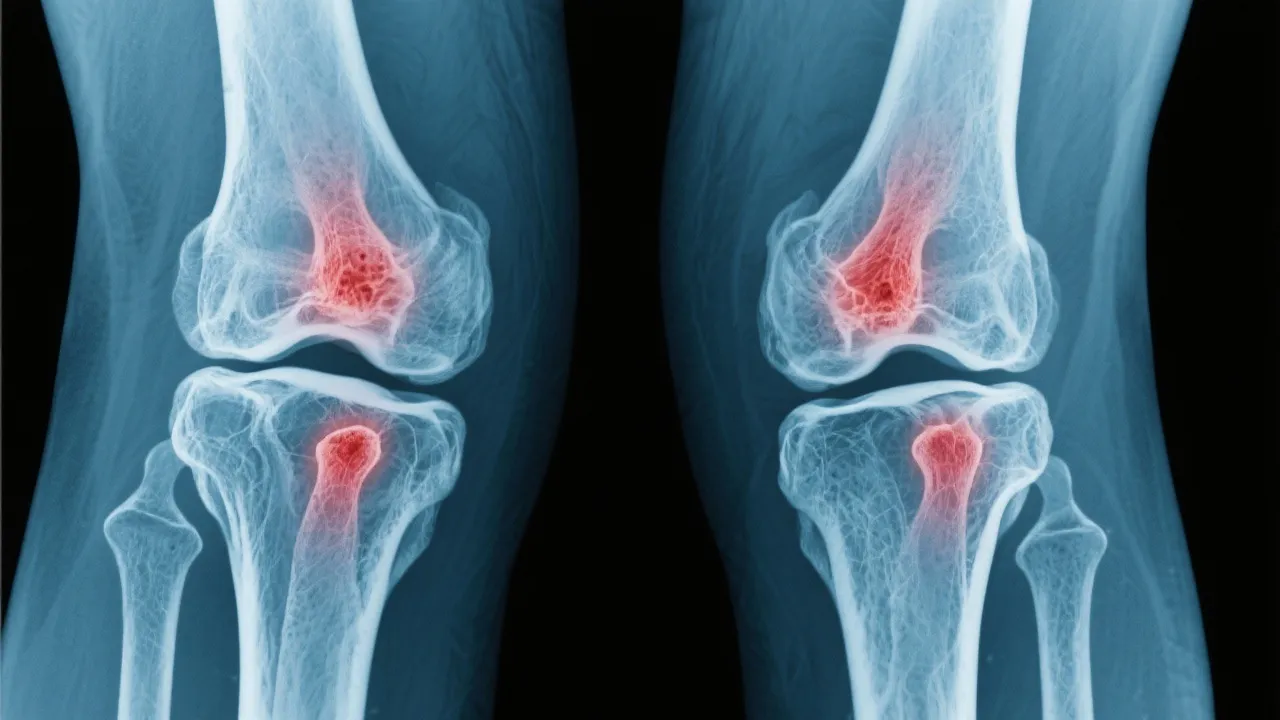

Addressing arthritis joint pain involves a detailed understanding of various treatment options designed to alleviate discomfort and improve quality of life. This article navigates through the landscape of arthritis treatment, exploring medical insights and evidence-based approaches to manage joint pain effectively. Examining arthritis, a prevalent condition impacting many, we dissect various methodologies employed to counteract the debilitating effects of joint inflammation.

Arthritis, a term encompassing over 100 different conditions, primarily involves inflammation of the joints. This condition is characterized by pain, stiffness, and swelling, which can significantly impair daily activities and quality of life. As individuals age, the prevalence of arthritis increases, making it a common concern among the elderly, though it can affect younger demographics as well. Arthritis can manifest in various forms and can impact not only the joints but also other organs in the body, causing systemic symptoms and complications. It is crucial to understand the underlying pathophysiology of arthritis to better appreciate how it affects individuals’ daily lives and the complexities involved in its management.